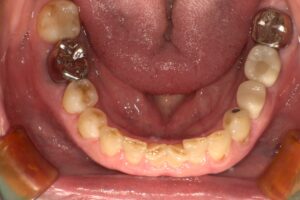

インプラント埋入後は、約3か月の治癒期間を設け、インプラントが骨としっかり結合していることを確認しました。その後、口腔内スキャナーを用いて上部構造製作のためのスキャニングを行い、最終的な被せ物を装着しました。

治療後は、「しっかり食事ができるようになった」「家族やお孫さんと一緒に外食を楽しめるようになった」とご満足いただくことができました。

現在も定期的にメンテナンスへ通院されており、インプラントを含めたお口全体の健康管理を継続しています。治療から数年が経過した現在も、安定した状態を維持されています。